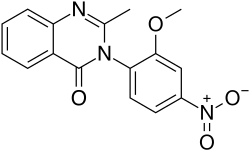

Quinazolinone

Quinazolinones are a class of depressants that are rarely used anymore. Quinazolinones have powerful sedative, hypnotic, and anxiolytic effects. Quinazolinone's structure is very similar to that of some antibiotics. Quinazolinone's main mechanism of action is binding to the GABAA receptor.[162] It does not bind to the ethanol, barbiturate, neurosteroid, or benzodiazepine site.[162] Instead, it binds on a site directly between the GABRB2 (β2) and (α1) GABRA1 proteins on the GABAA receptor.[162] The anesthetic etomidate and anticonvulsant loreclezole may also bind to this site.[162]

Methaqualone hydrochloride and quinazolinone anxiolytics and hypnotics are referred to as "quaaludes", "ludes", and "disco biscuits". Methaqualone was very commonly abused in the western world during the 1960s and 1970s. Methaqualone was mainly prescribed for insomnia, as it was thought to be safer than barbiturates and carbamates.[165] Methaqualone became highly abused by many, including celebrities, after its introduction in 1965.[163] Methaqualone was first synthesized in India in 1951 by Indra Kishore Kacker and Syed Husain Zaheer, who were conducting research on finding new antimalarial medications.[166][167] The drug name "Quaalude" (methaqualone) is a portmanteau, combining the words "quiet interlude". Methaqualone was discontinued in the United States in 1985, mainly due to its psychological addictiveness, widespread abuse, and illegal recreational use. Nonbenzodiazepines and benzodiazepines are now used to treat insomnia instead. Methaqualone is now a Schedule I substance. Some quinazolinone analogues are still sold online. They come with the risk of seizures.

Nitromethaqualone is a quinazolinone depressant with ten times more hypnotic and sedative effects than methaqualone.[174]

- Nitromethaqualone